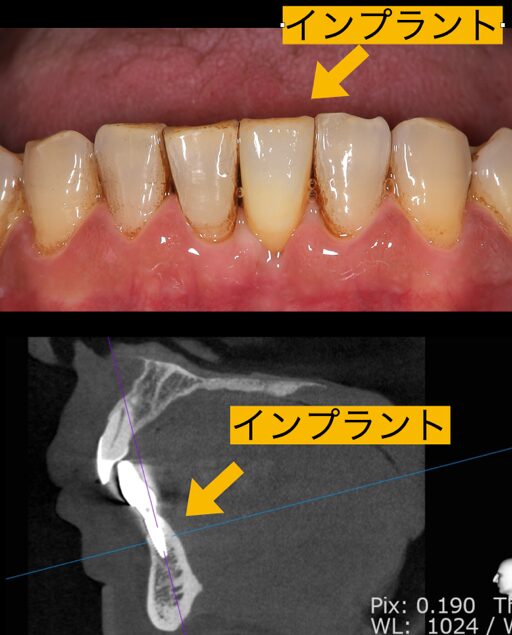

インプラント手術は抜いたその日に入る抜歯即時埋入で行いました。抜歯はすぐに終わったのですが、膿がかなりあり掻爬に時間がかかりましたが、ここをおろそかにするわけにはいきません。しっかりと膿取りを行い、デンザーバーで形成し細い2.8ミリのインプラントを埋入しました。

少し化膿しそうな治癒経過もありましたが、抗生物質を服用してもらい無事インプラントは生着しました。インプラントは細いですがこの細いインプラントは下の前歯と上の側切歯のみに使用できる太さなので適応を間違えなければ十分に強度は発揮できます。患者様も全く痛みなく治療を終えることができたので大変喜ばれていました。

コーヒーをよく飲まれる方なので、あとは最終的なセラミックにうっすらコーヒーのステインが付着すればもっと色調も揃ってくると思われます。